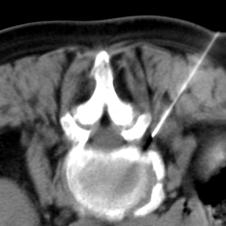

Die Periradikuläre Therapie ist die perkutane Infiltration von Medikamenten lokal an eine Nervenwurzel bei nachgewiesenen Verschleißerscheinung der Wirbelsäule.                                                                                       Unter Röntgendurchleuchtung oder Computertomographie wird gezielt die Schmerz verursachende Nervenwurzel mit einem speziellen Medikament behandelt.                                                                                             Die Anwendung erfolgt überwiegend bei ausstrahlenden Schmerzen ins Bein, bei Bandscheibenvorfällen und Schmerzzuständen nach Bandscheibenoperationen.